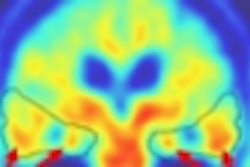

To evaluate FDG-PET in staging and assessing treatment response and cancer recurrence in SCLC, a Memorial Sloan-Kettering study team retrospectively reviewed 51 patients (67 scans) consisting of both treated (42) and untreated (9) cases. The imaging findings were correlated with pathology, CT/MRI, and clinical outcomes to determine sensitivity and specificity.

PET scanning was performed using an Advance PET scanner (GE Medical Systems, Waukesha, WI) following a six-hour fasting period and injection of 10 mCi of FDG. A pair of nuclear medicine physicians reviewed all cases; standardized uptake values (SUV) were calculated.

Overall, PET turned in a sensitivity of 90.2% with a specificity of 68.8%. In staging untreated cases, the scan findings concurred with final patient staging, Pandit-Taksar said. Mean SUVmax range in malignant cases was 7.6, while benign cases averaged 3.7. Both SUVmax (p=0.0075) and average SUV (p=0.0223) had significant negative association with survival, Pandit-Taskar said.